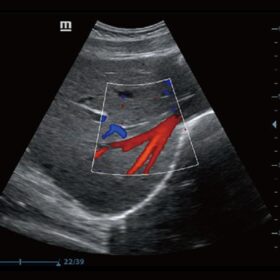

Ultrasound Mindray Z60 – Image Gallery

- B-Steer, Your tool for deeper biopsy: allowing adjustments to the scan line to gain better visibility of the needle, nerves and small vesselsies, guaranteeing the continuity of all data. With its carefully designed features, BeneView T1 perfectly matches these requirements.

- IMT (Intima-Media Thickness) Auto measurement of anterior and posterior wall thickness providing accurate carotid status.